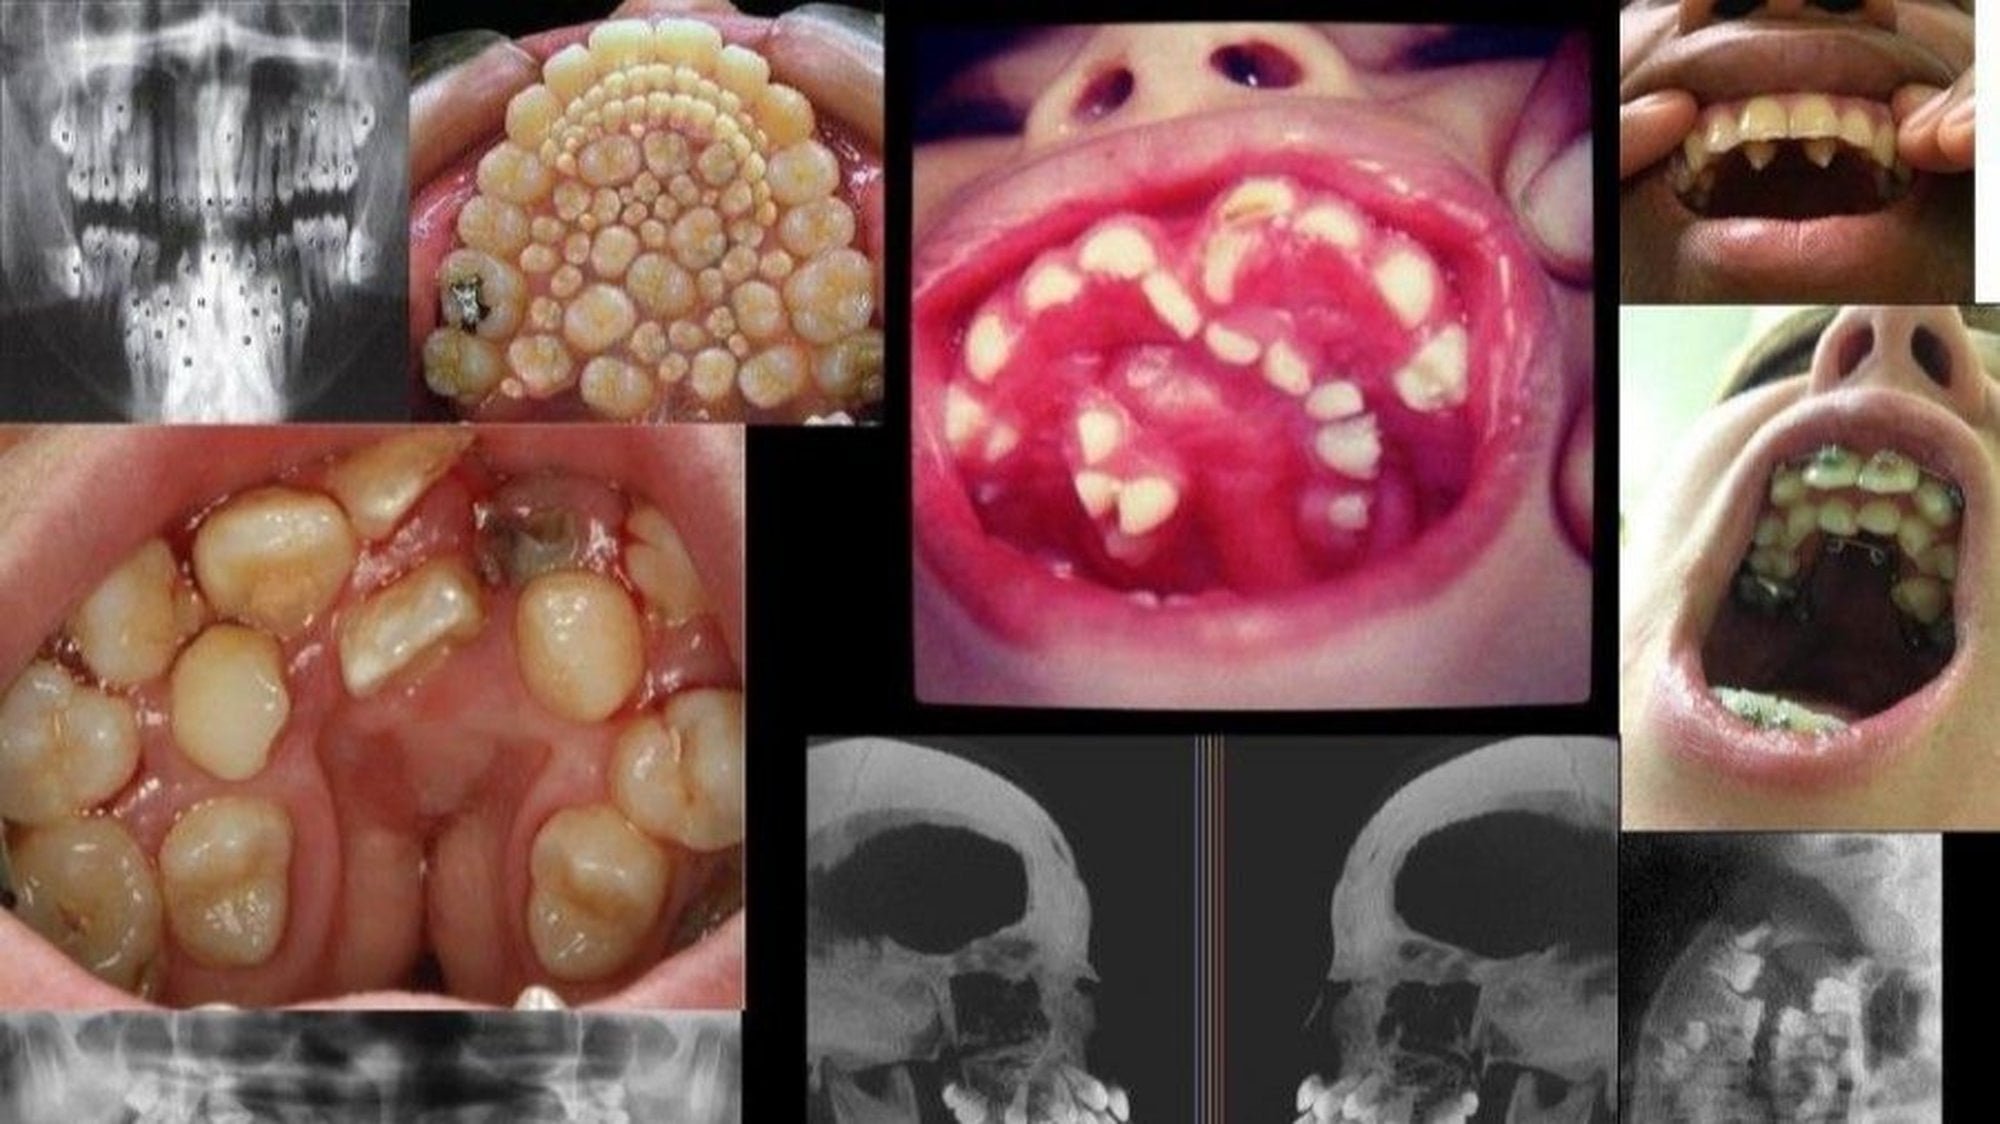

Hiperdontia birçok farklı formda karşımıza çıkar. En yaygın olarak görüneni ise meziyoden olarak bilinen, önde bulunan iki kesici dişimiz arasında ekstra dişlerin bulunmasıdır. Sonrasında ise fazladan öğütücü dişlerin bulunması, paramolar dişlerin bulunması (kesici ve öğütücü dişler arasında ekstra dişlerin gelişmesi), alt çene ön öğütücü dişlerin sayısının fazla olması, köpek dişlerinin sayısının fazla olması, vb. diş sayısı artışları gelir.

Fotoğrafta da gösterildiği gibi, birçok farklı hiperdonti türü bilinmektedir. Bunlardan sol üst köşede 2. sırada bulunan ve tüm damağın dişlerle kaplandığını gösteren fotoğraf sahtedir ve Photoshop ile üretilmiştir; dikkatli bakıldığında kendini tekrar eden dişlerin olduğu görülecektir. Ancak diğerleri gerçektir ve tıbben görülen hiperdonti vakalarına örnekler teşkil etmektedir.